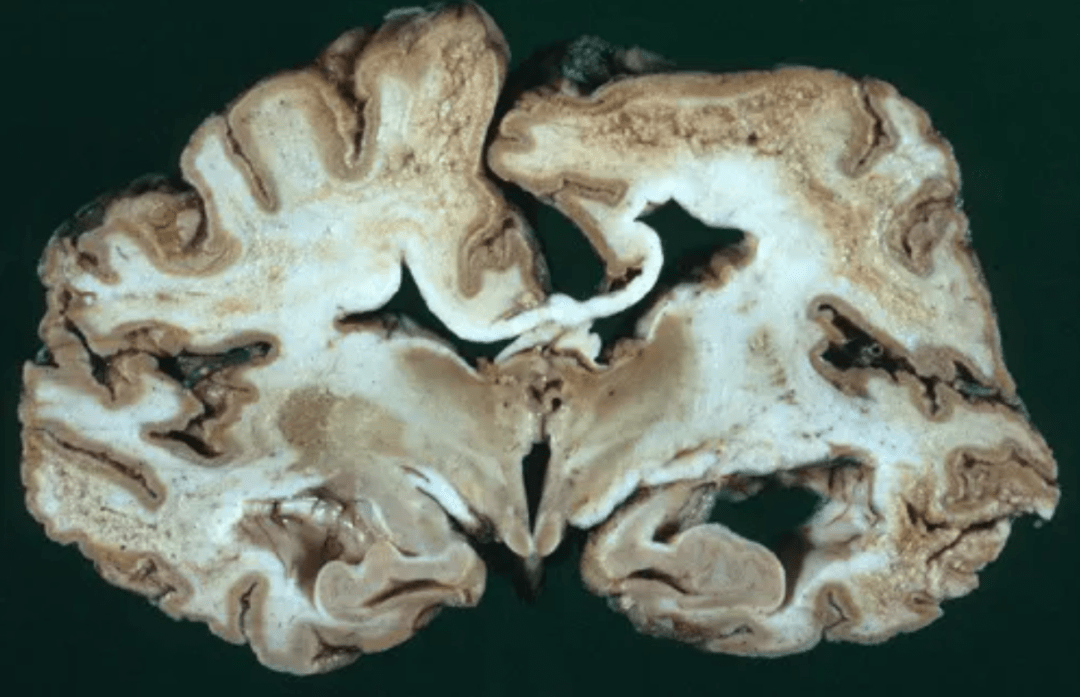

库鲁病大脑

图1-1 患有库鲁病的小孩